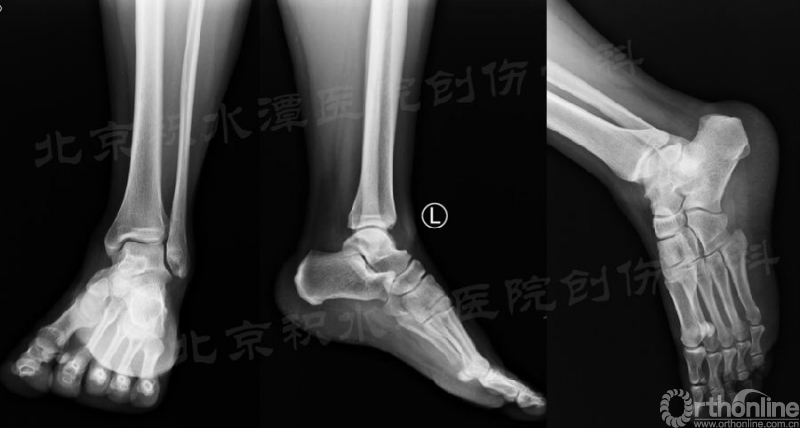

我们首先来看一例北京积水潭医院急诊室遇到的踝关节扭伤的病例。患者,女,43岁,急性病程,骑电动车停车时左足撑地时扭伤。既往左踝多次扭伤。

查体:坐轮椅于急诊就诊,左足不能负重。外踝肿胀,内踝无肿胀。外踝压痛,内踝无压痛;从内侧压后踝疼痛(内踝后缘外侧),从外侧压后踝轻微疼痛(Volkman结节)。

急诊常规拍摄X片:踝关节正侧位X线片无明显异常;但踝关节(或足)斜位可见后踝骨折无移位(不明显)。